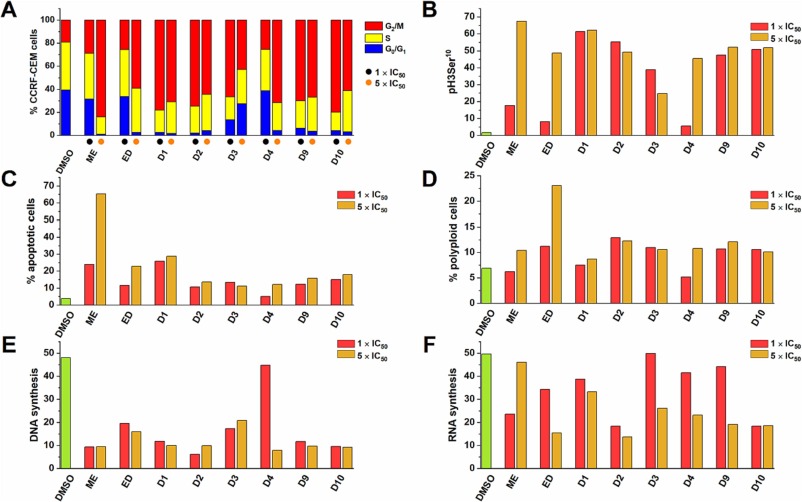

Single-cell protein profiling defines cell populations associated with triple-negative breast cancer aggressiveness.